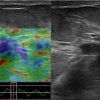

Ung thư vú

Ung thư vú - Ảnh 2

» Thông tin: Nữ giới – 50 tuổi.

» Lâm sàng: Khối tuyến vú.